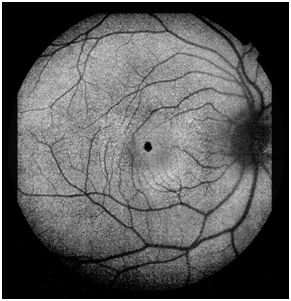

A 11-years-old Caucasian male presented with full visual acuity in both eyes (20/20). The patient underwent complete ophthalmic examination, spectral domain opticalcoherence tomography (SD-OCT), multicolour imaging, fundus autofluorescence (FAF) and OCT angiography (OCT-A). Fundus slit-lamp examination revealed a small, darkly pigmented, well-circumscribed lesion involving the central fovea in the right eye (Figure 1). With no clinical evidence of vascular/glial abnormalities. No abnormalities was found in the fellow eye. The FAF showed pronounced, homogeneus hypo-autofluorescence of the lesion (Figure 2).

Figure 2 Pronounced hypo-autofluorescence involving the central fovea.